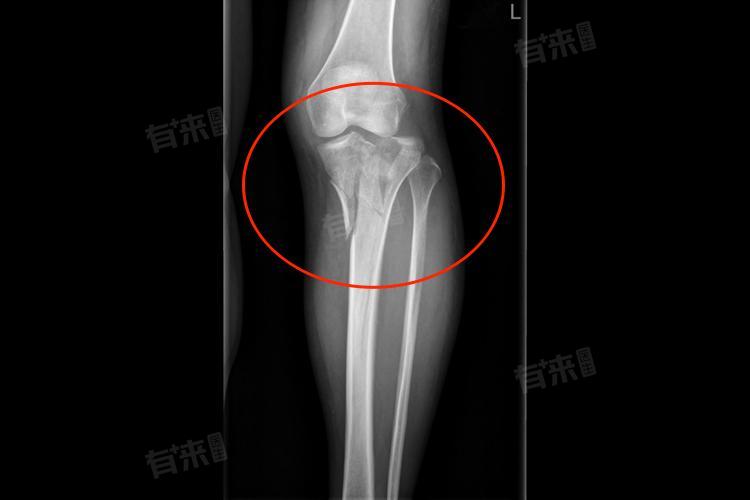

右胫骨平台骨折指右侧胫骨上端与股骨下端构成的膝关节重要负重区域发生骨结构连续性中断,是临床常见的关节内骨折。此损伤不仅破坏骨骼完整性,还可能累及关节软骨、韧带等结构,严重影响膝关节功能。

- X线检查:拍摄右膝关节正侧位X线片,初步判断胫骨平台是否存在骨折及骨折类型,观察骨折线位置、移位程度及关节面平整情况,为诊断提供基础依据。